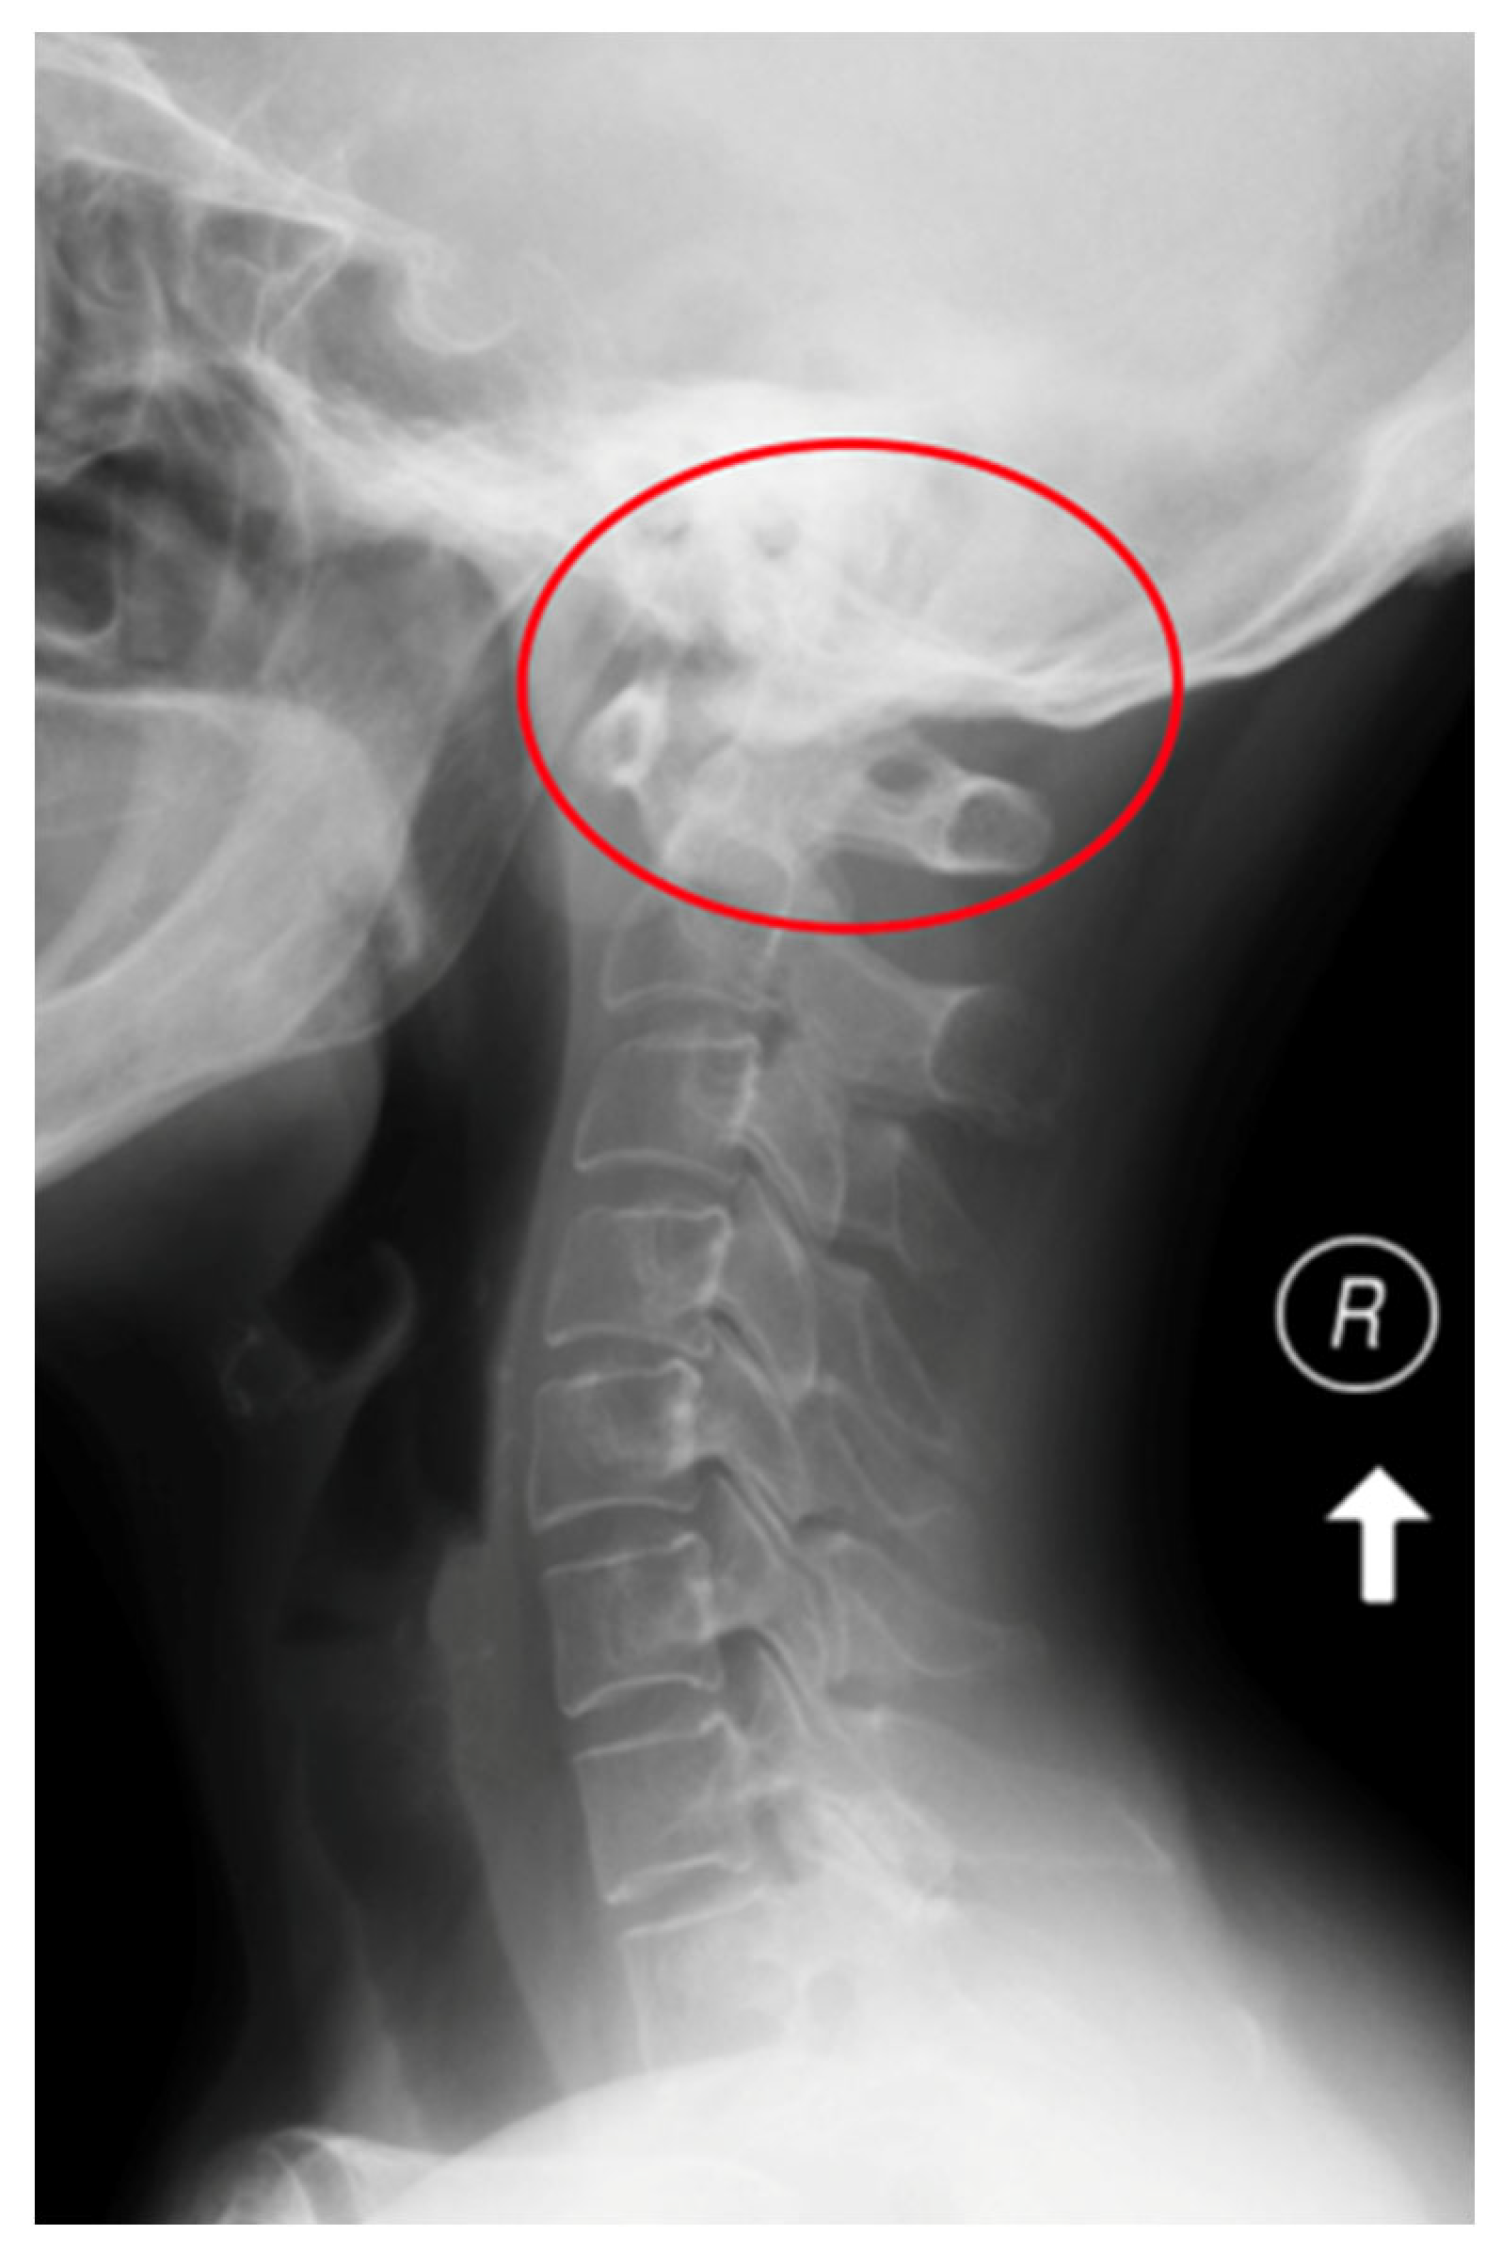

Figure 1.

An X-ray of the cervical spine (lateral view) of a 65-year-old female patient with RA and AAS instability.